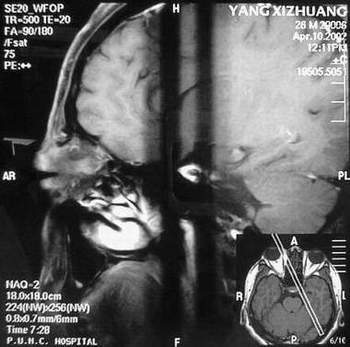

杨某,男,27岁。主因右眼进行性眼球突出一年。我院门诊就诊。发病来,患者无明显视物模糊,无视物成双。自觉无明显眼痛。五年前曾有食物中毒史。当地医院行CT检查,发现右眼眶鼻上方较高密度占位。

门诊检查:视力:双1.5。双眼各方向运动正常。右眼球向正前突出,其中颞侧更明显。右眼穹隆部结膜及近穹隆结膜血管扩张。右鼻上眶缘触及较饱满类结节物,压痛可疑。没有触及博动,听诊未及血管杂音。压迫颈静脉眼球凸度无明显改变。

B 超:球内未见明显异常回声,眶内可见血管暗影回声,视神经上下眶内周围软组织可见各一个血管暗影腔,眶内可见回声不均匀中度密度占位样回声。IMP: 眶内炎性病变?建议MRI除外动静脉瘘,血管性病变。

MRI及增强结果如下:

患者压颈及其它Valsava试验结果阴性。从MRI分析,在T1、T2、T+C检查该支血管均为明显流空现象,说明该血管血流速度很快,而从走行和分布看,眼上静脉可能性很大。也许也不能除外异常的眼动脉或异常血管。眶内主要可能的血管病变包括颈内动脉海绵窦瘘(高流窦)、AVM、眼眶静脉曲张、海绵状血管瘤、静脉性血管瘤、毛细血管瘤和眶内动脉瘤。。